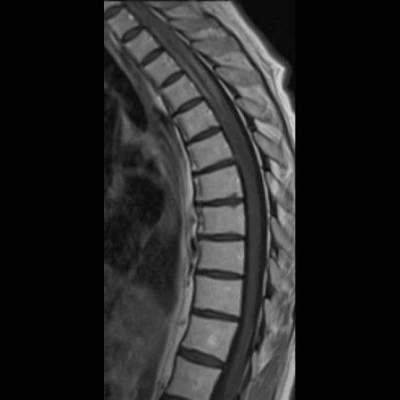

- (A) Torakal MRG’de sagital görüntülerde üst-orta torakal düzeyde T2A hiperintens (oklar), T1A izo-hipointens (ok) uzun segment ekspansil sinyal değişikliği izlenmekte olup sagital postkontrast T1A’da kontrast tutulumu mevcuttur (oklar). Bulgular longitudinal ekstensif transvers miyelit (LETM) ile uyumludur.

- Transvers miyelit sıklıkla santral gri cevheri etkileyen ve üç veya daha fazla vertebral gövde uzunluğunu etkilemektedir (LETM).

- Transvers kesitlerde, santral kordu tutma eğilimindedir.

- Omurilik atrofisi ve ekspansiyon/ödem MS’e göre daha fazla görülür.

- Kontrast madde enjeksiyonu sonrasında neredeyse tüm akut NMO lezyonları, yamalı, düzensiz veya periferik olarak kontrastlanma gösterir.